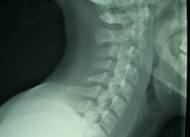

When you want to be properly diagnosed about your neck and jaw pain, expect to answer a set of questions that will be able to give the doctor a clear idea of what you are feeling. You will also need to undergo a series of MRIs to view the nerves and the spinal cord, x-rays (dental problem) if you have bone spurs or protruding disks, EMG to assess nerve function, and CT scan (for TMJ diagnosis), to view the sections of internal anatomical structures.